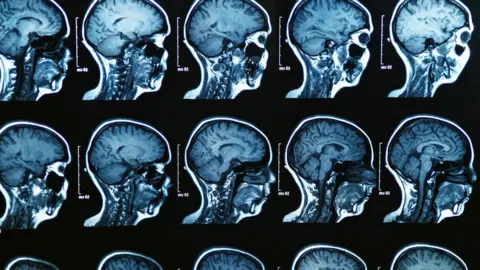

Getty ImagesDigital diagnostic tools such as this that use AI, are springing up to help tackle all kinds of health conditions. Such as pattern-recognition technology assisting the detection of cancers, or analysing the brain scans of acute stroke patients.